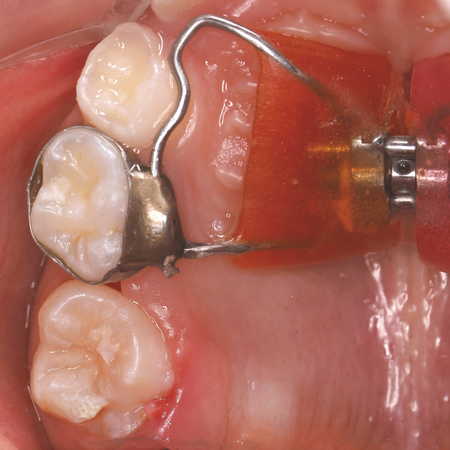

The use of a Haas expander to intercept an ectopic eruption of a maxillary permanent first molar

OBJECTIVE: The aim of this article is to present a clinical case of a 7-year-old patient who underwent maxillary expansion with the Haas expander and, after 10 months of follow-up, ectopic eruption of the upper right permanent first molar was identified using a panoramic radiograph. CASE REPORT: The proposed treatment was to use the same expander to disimpact the ectopic molar. The appliance was removed and a rigid wire extension was soldered to the ring of the deciduous second molar, with a...